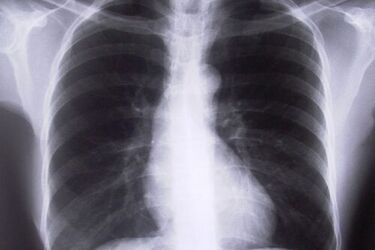

Fot: sxc.hu

Obowiązują nowe przepisy dotyczące radiologów. Dłuższy czas pracy nie oznacza jednak dodatkowych pieniędzy.

Od 1 lipca 2014 r. obowiązuje o połowę wyższy wymiar czasu pracy dla radiologów. Niestety za zwiększeniem godzin pracy nie zmieniło się nic w kwestii zarobków. Jeszcze wiosną oburzało to radiologów. Wcześniej pracowali pięć godzin dziennie i zarabiali 16 zł na godzinę. W pracy specjaliści zajmują się m.in. wykonywaniem badania USG oraz opisami wyników. Po zmianie przepisów specjaliści muszą pracować po 7,5 godziny dziennie.